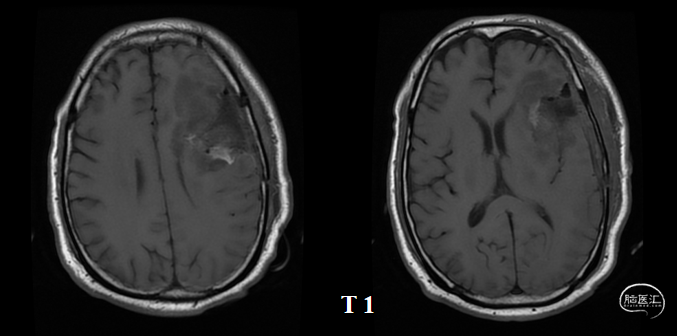

放疗后17月(2021-12-20)MRS显示左颞叶感兴趣区Cho/NAA约1.19-5.53:图示。

放疗后17月(2021-12-20)PWI显示感兴趣区脑血容量及血流量较对侧高低不一,平均通过时间及达峰时间延长,提示左侧病变区血流灌注降低:图示。

再次经MDT讨论,考虑假性进展可能,继续肿瘤电场治疗。

术后5周开始实施标准的新STUPP方案的辅助治疗,即在同步放化疗后,辅助替莫唑胺化疗的同时使用了电场治疗。目前生存25月,且临床和影像学表现均提示稳定,未见复发迹象。期间,在放疗后7月时复查MRI提示异常FLAIR信号区增大,经我院MDT讨论,考虑到强化信号减轻,无明显占位效应,患者无症状体征,考虑是治疗后水肿,非进展,故继续按原方案治疗。放疗后17月复查MRI出现术区边缘局部强化范围稍增大,但PWI示强化区局部呈低灌注且未见弥散受限表现,MDT讨论考虑为假性进展,继续原方案治疗。后续复查MRI强化范围减轻,证实了MDT的判断证实疾病稳定。患者生存时间已达25个月。全程安全顺利,仅出现一过性轻度皮肤反应。

辅助TMZ治疗过程中每2-3月复查MRI。治疗中曾出现水肿范围增大,尽管有部分区域弥散受限和MRS异常及血流量增加,但是临床症状未加重,仍继续原方案治疗,后续监测PWI显示病变区灌注减低。提示持续肿瘤电场治疗可以使病变长期稳定。此患者每天佩戴肿瘤电场治疗时间接近22小时,中间出现头皮发红和小水泡,经局部外用皮质类固醇和外用抗生素,暂停2天治疗恢复。至今随访25月稳定。说明肿瘤电场治疗联合TMZ治疗较单TMZ治疗明显延长胶质母细胞瘤患者PFS及OS,临床应积极推广使用。